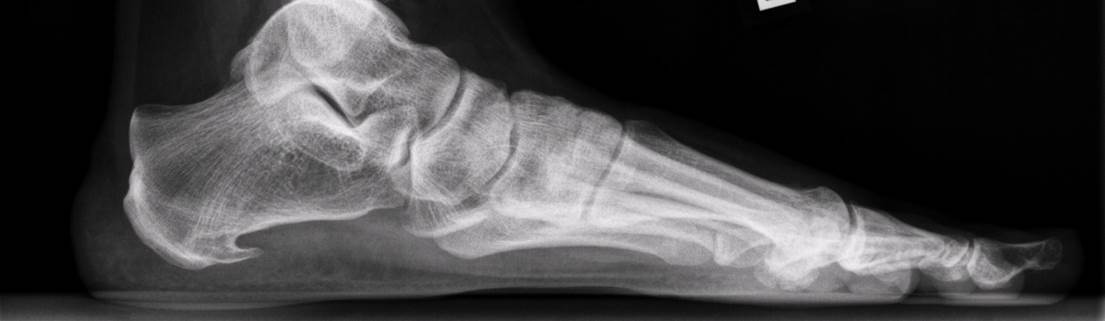

Een hielspoor is een botuitwas (verkalking) aan de onderzijde van het hielbot, het zogenoemde calcaneus. Deze verkalking bevindt zich op de plaats waar de peesplaat onder de voet, de fascia plantaris, aanhecht. Een hielspoor is goed zichtbaar op röntgenfoto’s en kan ook met echografisch onderzoek worden vastgesteld.

Hielspoor op röntgenfoto

Hielspoor duidelijk zichtbaar op deze op röntgenfoto.